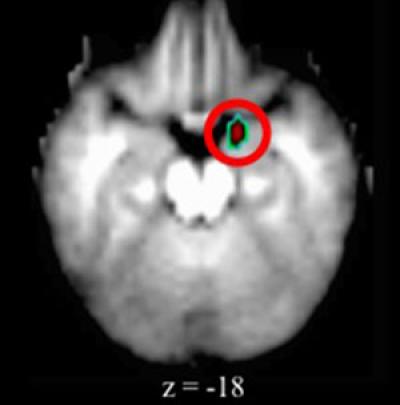

A key brain structure that regulates emotions works differently in preschoolers with depression compared with their healthy peers, according to new research at Washington University School of Medicine in St. Louis.

Depressed preschoolers had elevated activity in the brain's amygdala, an almond-shaped set of neurons important in processing emotions. Earlier imaging studies identified similar changes in the amygdala region in adults, adolescents and older children with depression, but none had looked at preschoolers with depression.

"The amygdala region showed elevated activity when the depressed children viewed pictures of people's faces," said Gaffrey, an assistant professor of psychiatry. "We saw the same elevated activity, regardless of the type of faces the children were shown. So it wasn't that they reacted only to sad faces or to happy faces, but every face they saw aroused activity in the amygdala."

In the preschoolers with depression, all facial expressions were associated with greater amygdala activity when compared with their healthy peers.